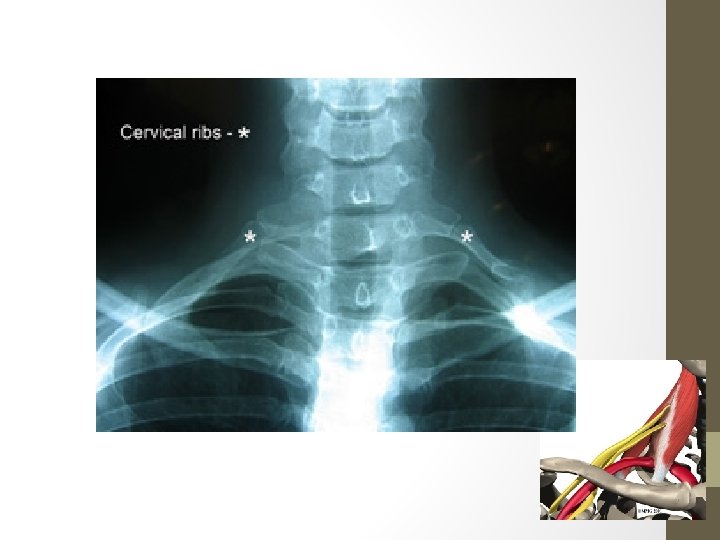

Pathophysiology • BY STRUCTURE CAUSING CONSTRICTION • Classify TOS by the location of the obstruction: • Scalenusanticus syndrome = Compression on brachial plexus and/or subclavian artery caused by muscle growth Diagnosed by using Adson's sign with patient's head turned outward. • Cervical rib syndrome = Compression on brachial plexus and/or subclavian artery caused by bone growth Diagnosed by using Adson's sign with patient's head turned inward.

Pathophysiology • Costo-clavicular syndrome = Narrowing between the clavicle and the first rib. Diagnosed with the costo-clavicular manoeuvre. • Some people are born with an extra incomplete and very small rib above their first rib, which protrudes out into the superior thoracic outlet space. • Causes fibrous changes around the brachial plexus nerves, inducing compression and causing the symptoms and signs of TOS. • This is called a "cervical rib" because of its attachment to C-7 and its surgical removal is almost always recommended. The symptoms of TOS can first appear in the early teen years as a child is becoming more athletic.

Illustrations / X-Rays